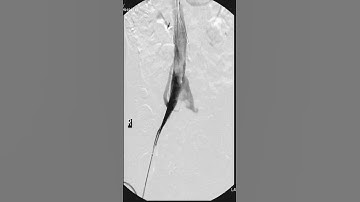

IVC Thrombus- Level 1- 4: Tips & Tricks (Open/Lap/Robotic)